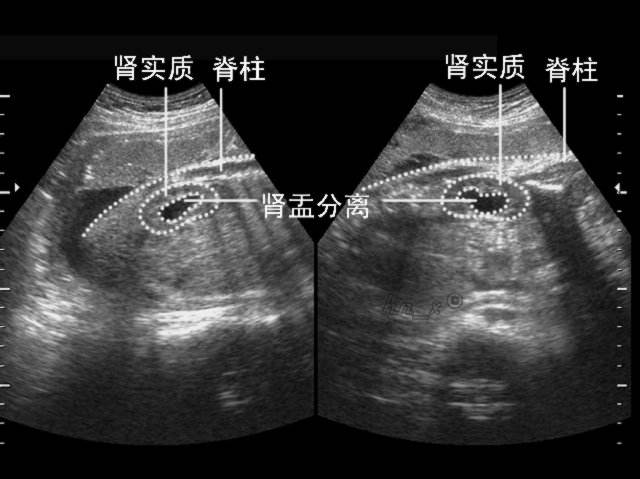

肾盂分离是什么意思,肾盂在哪个位置图片

肾盂分离是肾积水吗 严重才会导致肾积水

胎儿肾盂分离

双肾盂分离

肾盂分离

肾盂分离图解

肾盂分离图片